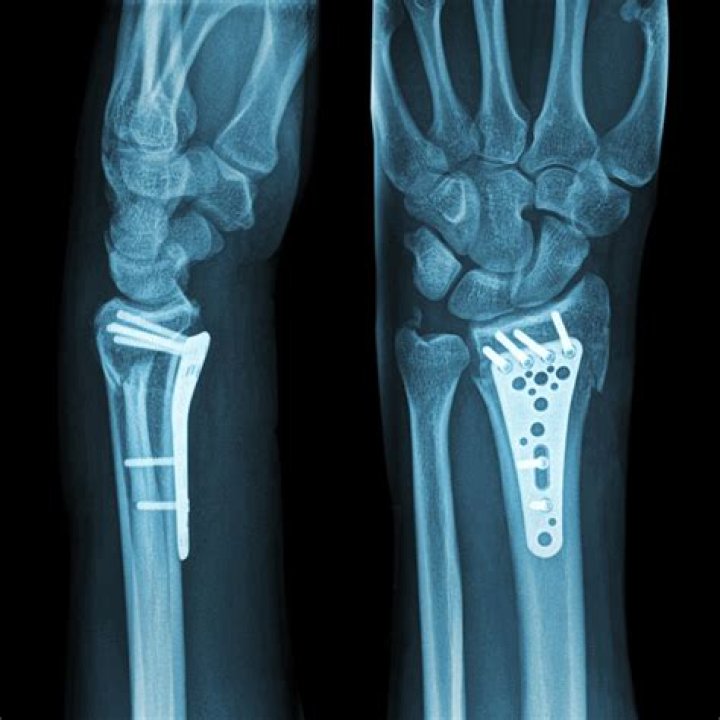

Does a distal radial fracture require surgery?

When a distal radius fracture is complex or unstable, it will most likely require a surgical approach to ensure the fracture stays in place during the healing process.

How do you fix a distal radius fracture?

Nonsurgical Treatment If the distal radius fracture is in a good position, a splint or cast is applied. It often serves as a final treatment until the bone heals. Usually a cast will remain on for up to six weeks. Then you will be given a removable wrist splint to wear for comfort and support.